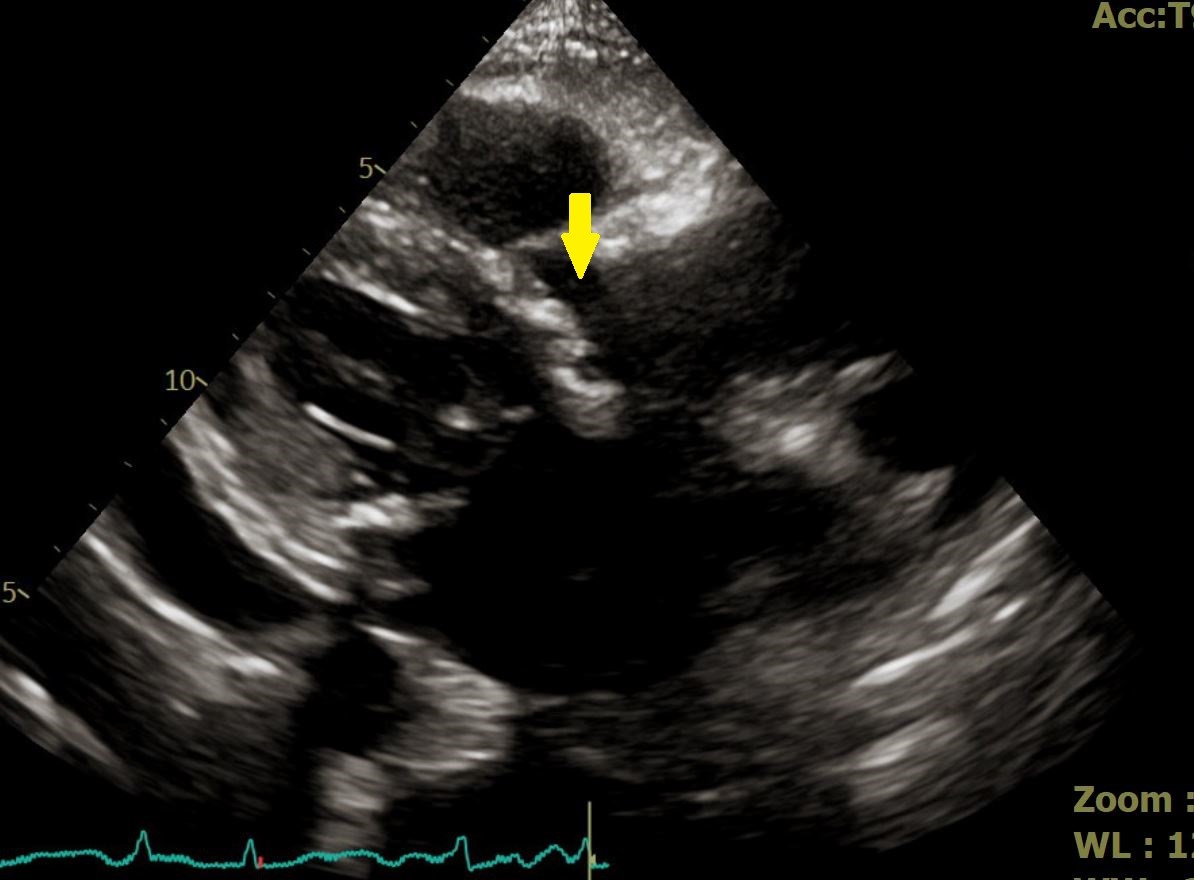

▲羅勖中醫師指出,病患主動脈瓣膜嚴重鈣化,幾乎無法讓血流流過。

【記者 劉芳妃/嘉義市 報導】90歲高齡婦人因反覆出現肺水腫及下肢水腫住院治療,病情穩定後出院,返家後仍持續感到走路喘、雙腳腫脹,甚至無法平躺入睡,只能長時間坐著休息,生活品質大受影響。家屬陪同前往衛生福利部嘉義醫院心臟內科門診就醫,經心臟內科羅勖中醫師詳盡問診與檢查,發現該名婦人具有明顯心臟衰竭症狀。安排心臟超音波檢查後,確診為「嚴重主動脈瓣膜狹窄」,屬於高齡族群常見且具高度風險的結構性心臟疾病,轉台中榮總接受經導管主動脈瓣膜置換,已平安出院返家休養。

羅勖中醫師指出,主動脈瓣膜狹窄會導致心臟無法有效將血液打出,進而引發肺水腫、呼吸困難、走路喘,嚴重時甚至可能導致休克。若未及時治療,重症患者一年內死亡率可高達五成。儘管患者年事已高,但羅醫師綜合評估其整體身體狀況、心臟衰竭嚴重程度後,認為其仍適合接受經導管主動脈瓣膜置換術(TAVR)。